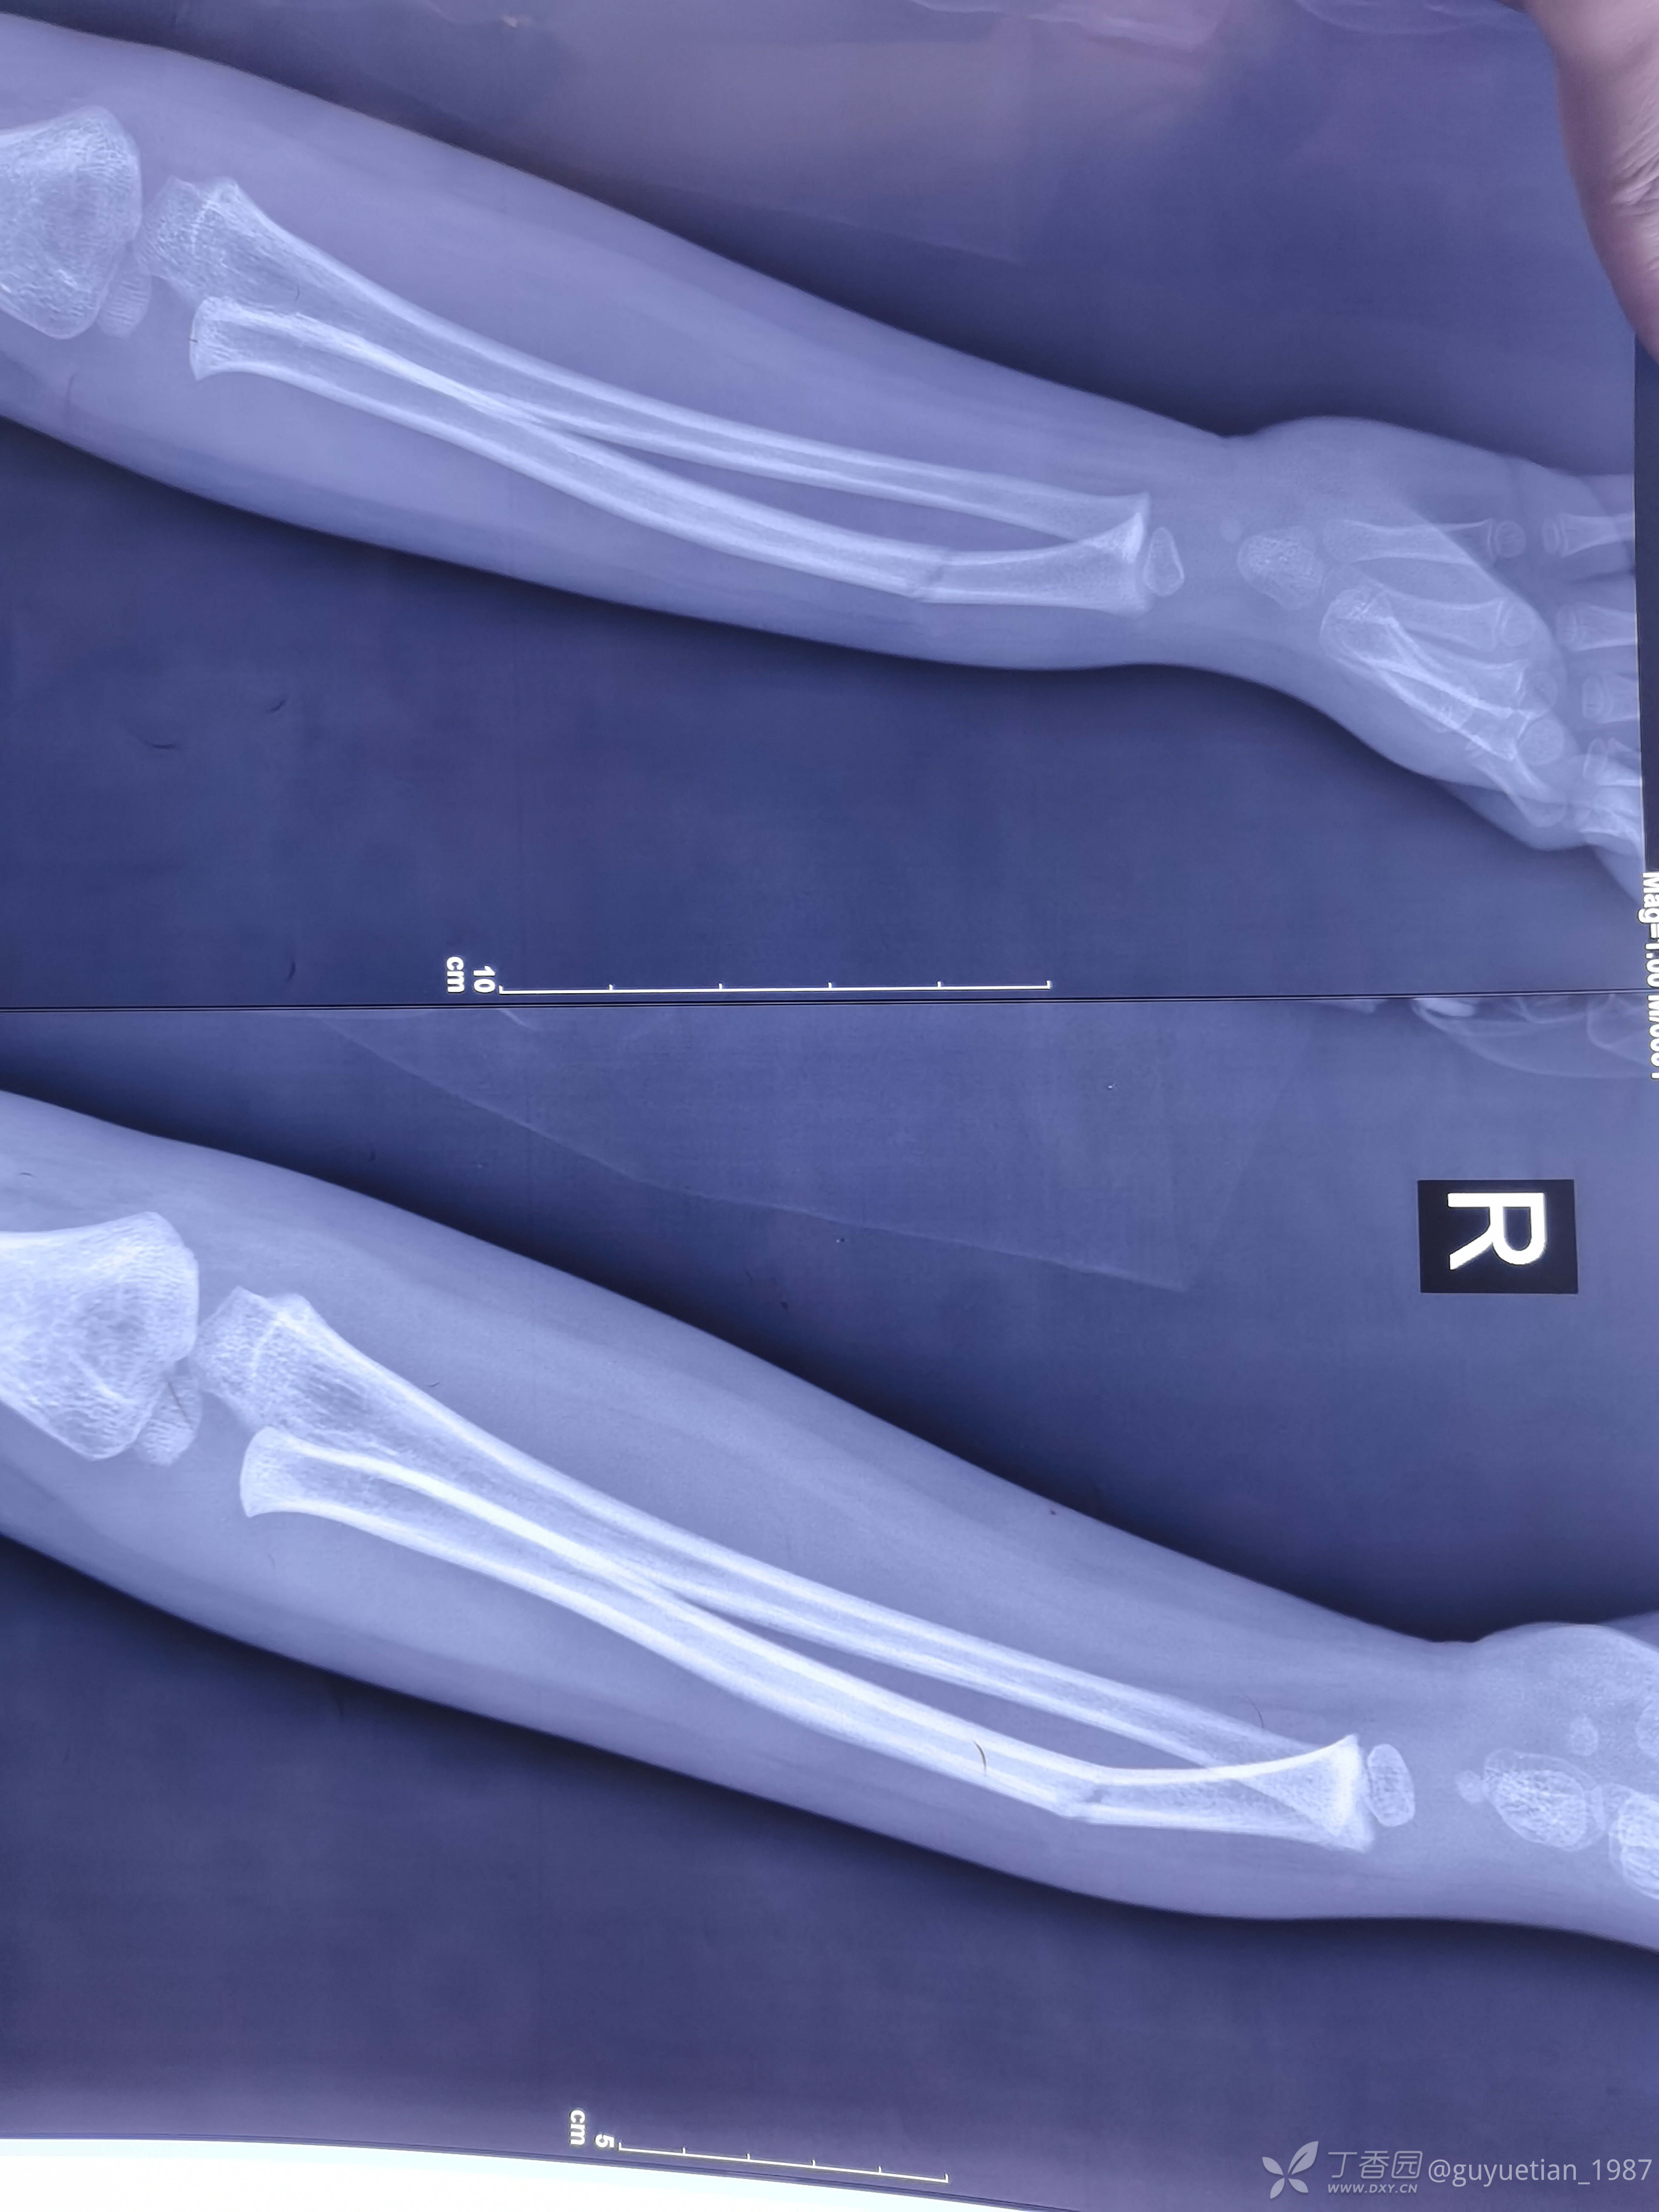

二次骨折,儿童前臂骨折(相信孩子塑形潜能)

患儿6岁,夜急诊遇见他前两月余同一手臂桡骨青枝骨折,保守治疗后顺利愈合。

果然儿童前臂骨折很容易发生二次骨折。夜急诊来院,尺桡骨中远1/3双骨折。即刻复位,自制小夹板旋后位固定,复位并不理想,与家属沟通病情(手术与保守的利弊),家属充分理解后选择保守治疗。